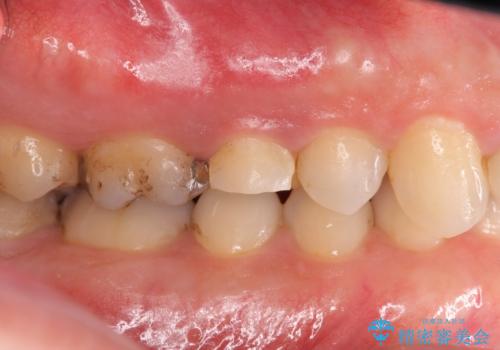

術前・術後でブリッジ治療をした部分の歯肉ラインを整えたことで安定したブリッジを製作することができました。

強い咬合力クリアランスの問題を解決したメタルボンドブリッジ治療